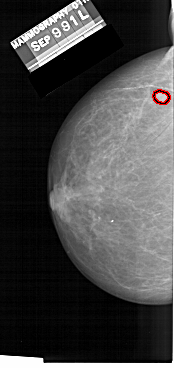

A_1481_1.LEFT_MLO

LEFT_MLO LINES 6871 PIXELS_PER_LINE 3346 BITS_PER_PIXEL 12 RESOLUTION 43.5 OVERLAY

FILE: A_1481_1.LEFT_MLO.OVERLAY

TOTAL_ABNORMALITIES 1

ABNORMALITY 1

LESION_TYPE MASS SHAPE ROUND MARGINS CIRCUMSCRIBED

ASSESSMENT 3

SUBTLETY 4

PATHOLOGY BENIGN

TOTAL_OUTLINES 1

BOUNDARY